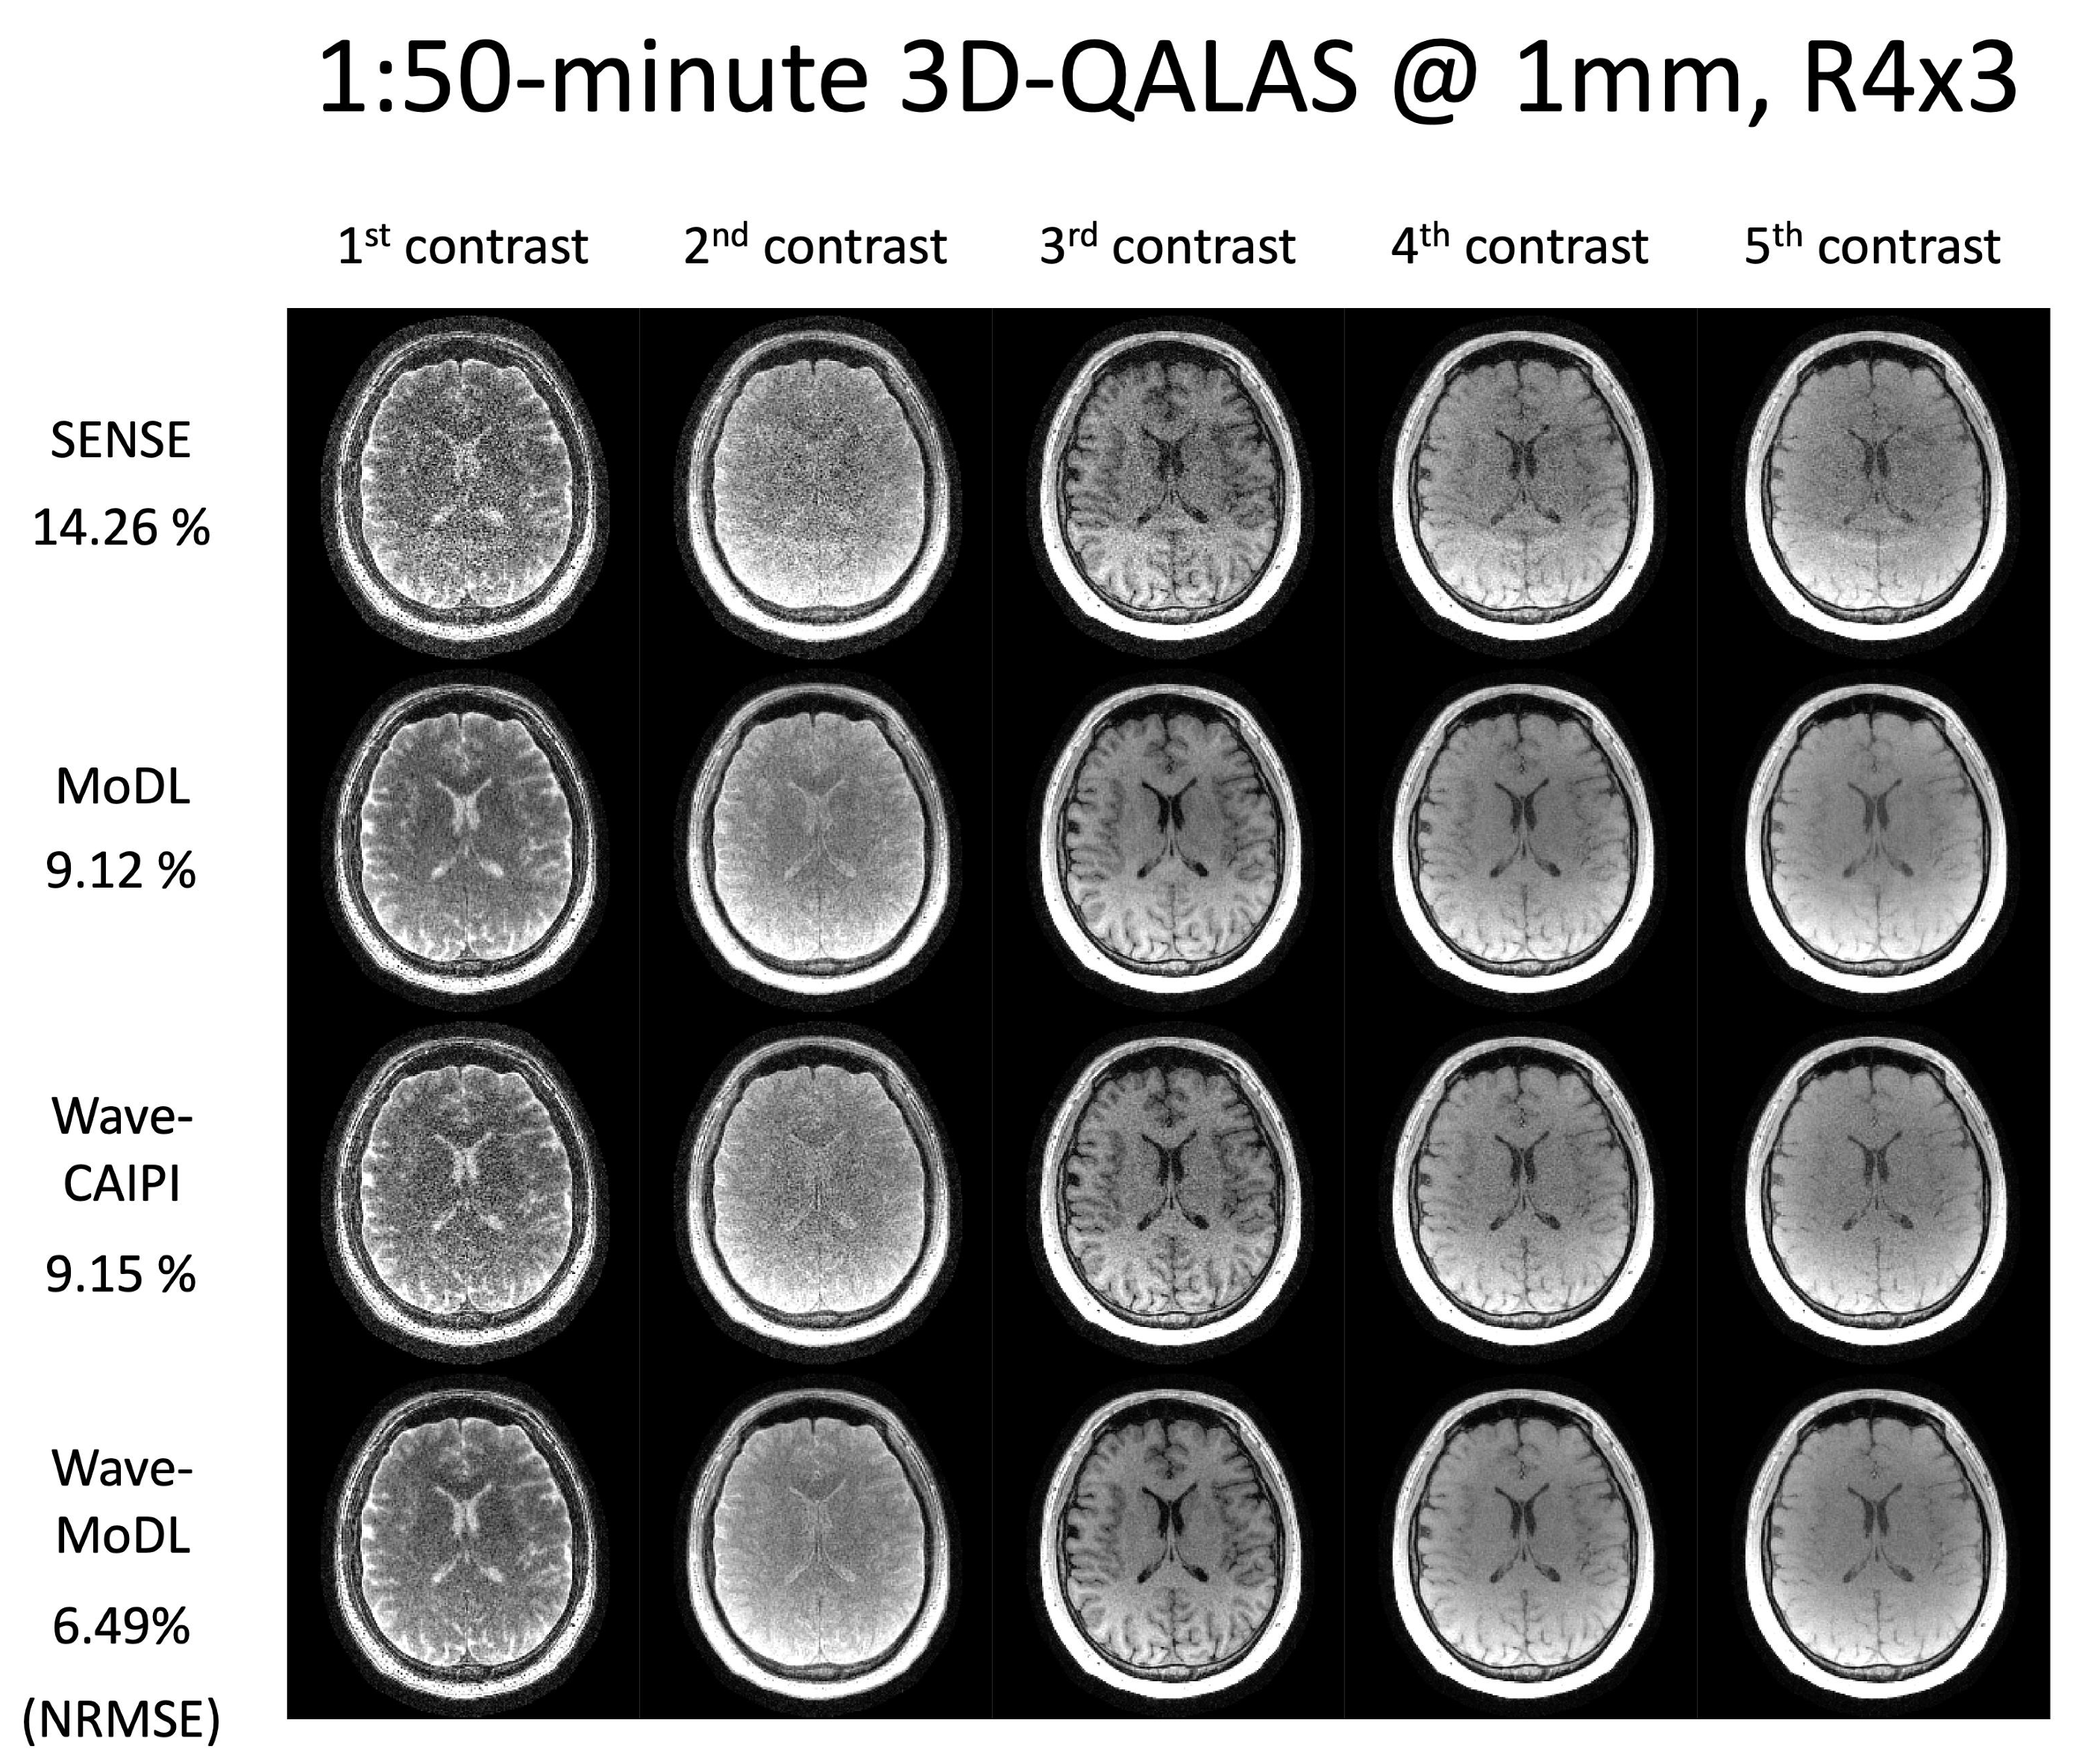

4.3. 3D-QALAS at R = 4 × 3